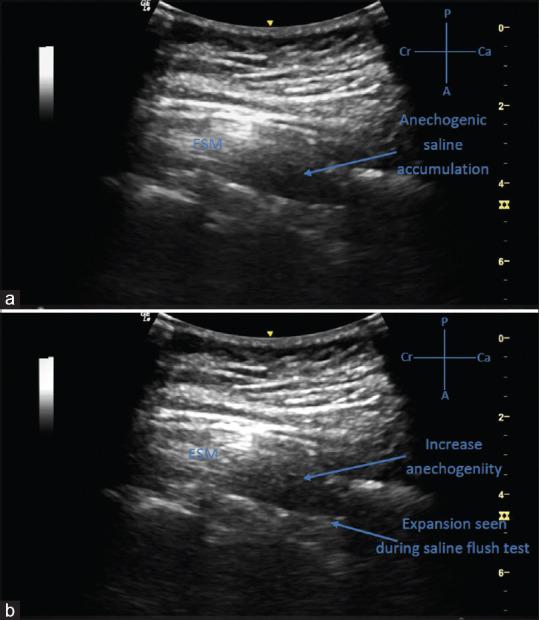

RESULTS

The pre-procedural UVS by the transverse interlaminar view (x/21) was 2.81 ± 1.94 and by the oblique paramedian sagittal view was 16.66 ± 2.39 with UVS being best in the paramedian oblique sagittal view (P- value < 0.05). The comparison of depth of the epidural space identified by USG and that by the LOR technique was statistically insignificant (P = 0.83). The average puncture attempts were 1.1 ± 0.3. Post-procedure US epidural catheter confirmation score (x/3) was 1.44 ± 0.44 with either epidural space expansion or microbubbles seen or both.

结果

横突间矢状视图(x/21)的术前 UVS 为 2.81±1.94,斜旁正中矢状视图为 16.66±2.39,旁正中斜矢状视图的 UVS 最佳(P<0.05)。USG 测量的硬膜外空间深度与 LOR 技术测量的深度无统计学差异(P=0.83)。平均穿刺尝试次数为 1.1±0.3。术后 US 硬膜外导管确认评分(x/3)为 1.44±0.44,可见硬膜外空间扩张或微泡或两者均可见。